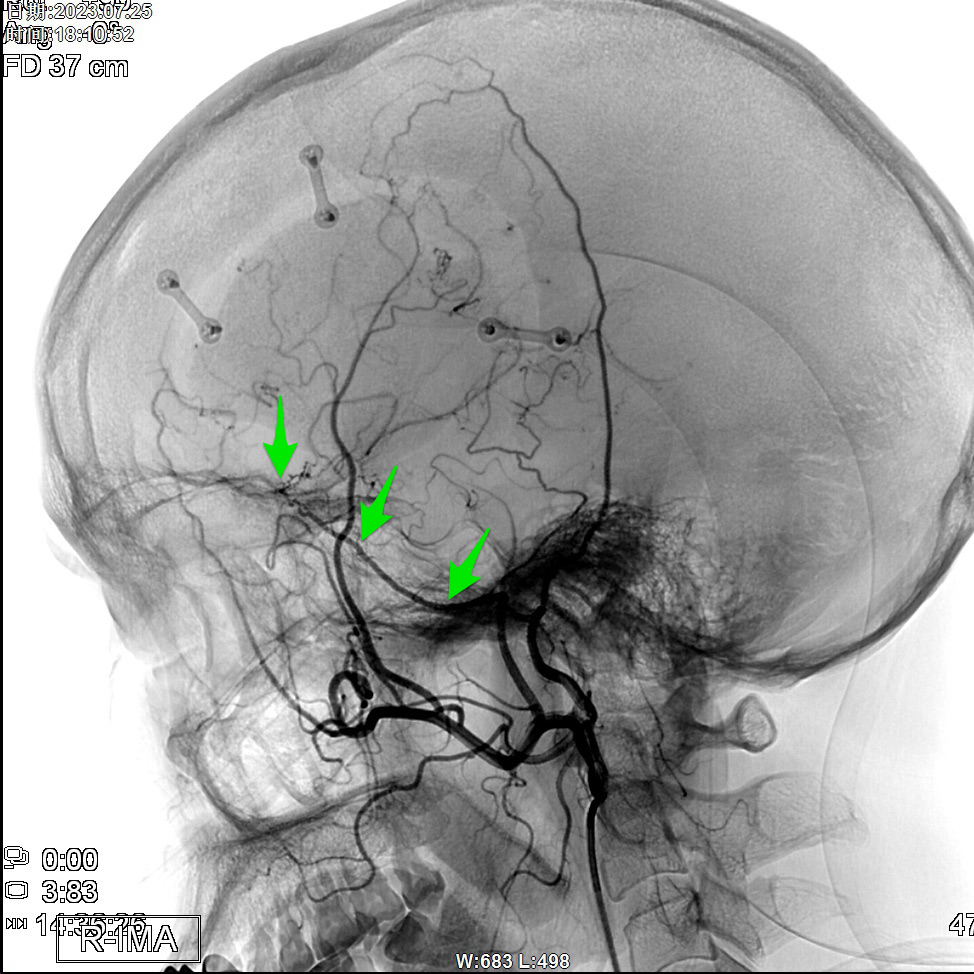

昆明三博2023:颞浅动脉一大脑中动脉M3吻合术